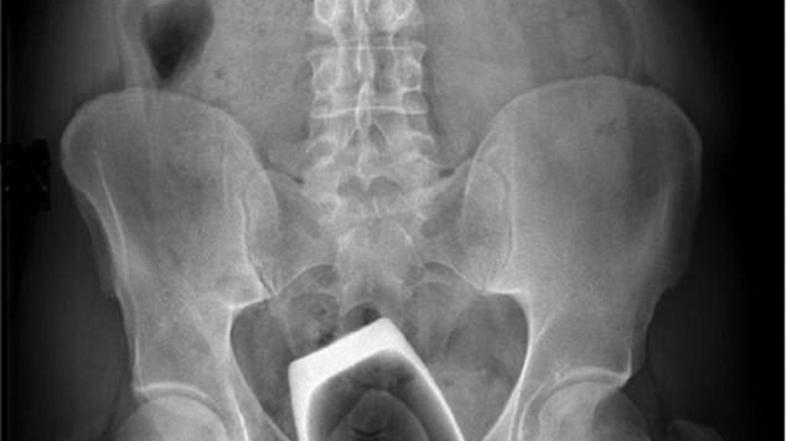

rentgen, kozarec Reševalni pas/Twitter

Italijan si je v anus porinil stekleni predmet, za večji seksualni užitek.

Neimenovani italijanski državljan si je v anus vstavil stekleni kozarec, širok 6 centimetrov in visok 8 centimetrov. Zdravnikom je povedal, da si ga je ustavil za boljšo stimulacijo pri spolnih odnosih. Ko ga je želel odstraniti, se je kozarec v anusu zdrobil.

Zdravnika je obiskal šele dva dni kasneje, saj ga je skrbelo za svoje zdravje, čeprav ni občutil nikakršnih bolečin.

Pacienta so takoj odpeljali v operacijsko, kjer so mu odstranili delčke kozarca. Bolnišnica mu je ponudila tudi psihiatrično pomoč, a jo je pacient zavrnil in se vrnil v zavetje svojega doma.